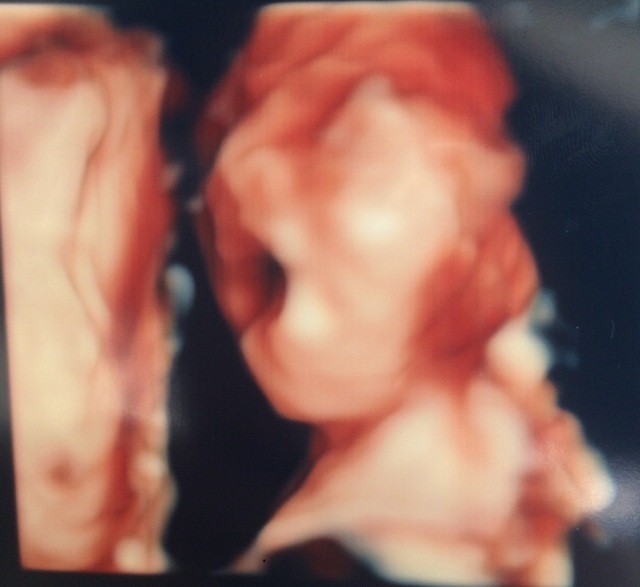

21週0日(21w0d・男の子)|Erimak さん(32歳)

エコー写真撮影時のエピソード:

もぞもぞと胎動が分かり始めしゃっくりもよくしていました!4Dをしてお顔を見せてくれた日でした。

もぞもぞとよく動き疲れたのか大きなあくびをした瞬間のエコー写真です。 お顔を見せてくれた感動とあくびをしている神秘的な姿にも感動した日でした